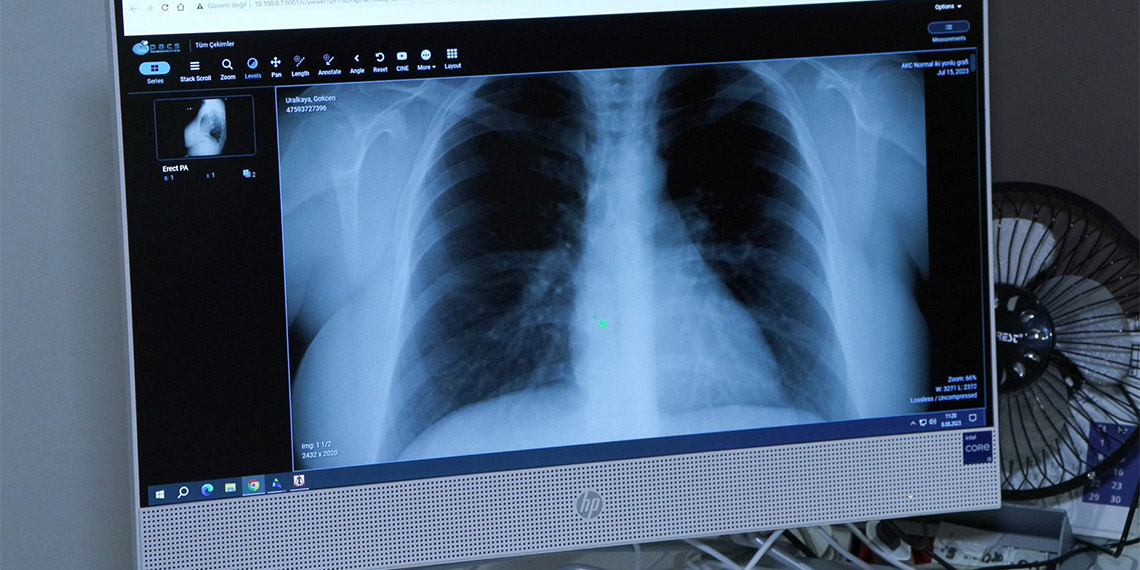

Medicana Çamlıca Hastanesi Göğüs Hastalıkları Uzmanı, Dr. Hacer Ofluoğlu, Afrika sıcaklarıyla akciğer ve alerji hastalıklarının arttığını belirtti.

Türkiye’de yaşanan Afrika sıcaklarının kişilerde kronik akciğer ve alerjik hastalıkları tetiklediğini belirten Göğüs Hastalıkları Uzmanı, Uzman Dr. Hacer Ofluoğlu, “Geçen yaza oranla acile ve göğüs polikliniklerine başvurular arttı. Sadece görev yaptığım hastanede bile yapılan alerji, solunum fonksiyon testlerinde yüzde 25-30 artış saptadım. Özellikle şu ana kadar hiçbir akciğer ve alerji sorunu olmayan kişilerde yükselen rakamlar tespit ettik. Bu da yüzde 10 arttı” dedi.

Aşırı sıcak hava dalgaları, yoğun nem, birden gelişen ısı değişimi ve rüzgârla bir gelen tozun kronik akciğer ve alerjik hastalıkları tetiklediğini söyleyen Medicana Çamlıca Hastanesi Göğüs Hastalıkları Uzmanı, Uzm Dr. Hacer Ofluoğlu, “Aşırı sıcaklar bu tür hastalıkların ortaya çıkma olasılığını son yıllarda artırmaktadır.

Polenlerin çöl tozlarıyla uzun mesafeler sürüklenmesi, aerosollerin alerjik hastalıkları daha uzun süreler karşımıza çıkarması, sadece polen dönemlerinde ya da mevsimsel alerjik dönemlerde değil yılın farklı mevsimlerinde de artık ortaya çıkma ve karşılaşma olasılığımızı artırmaktadır. Sıcaklıkların ve nemin artışı, kronik akciğer hastalıklarında da solunum yollarında mukozanın ısınması ve öksürük semptomlarına yol açıyor” açıklamasında bulundu.

Uzm Dr. Ofluoğlu, “Sağlıklı bir solunum yapabilmemiz için ortamda istenilen nem düzeyi yüzde 30 ila 50’dir.Son yıllarda artan nem düzeyleri ise öksürük, nefes darlığı, hırıltı, alerjik limit belirtilerinde kötüleşme yani özellikle hapşırık ve burun tıkanıklığı vakalarında artışa neden olmuştur. Bunlar mukoza üzerinde ısınma, nemin yapmış olduğu mukozal hasar, mukoza miktarlarının artışı ve mukus kıvamının koyulaşması nedeniyle bu tür belirtileri hastanın akciğerde daha fazla hissetmesine yol açmaktadır. Çöl tozlarıyla sürüklenen polenler, mantar sporları, virüsler, bakteriler uzun süre havada asılı kalabiliyor. Sağlıklı akciğerde dahi solunumsal semptomları artırabiliyor. Bunun yanında özellikle kronik akciğer sorunu olanlarda bu tür semptomların şiddetlenmesine ve acil başvurularının artışına neden oluyor” dedi.